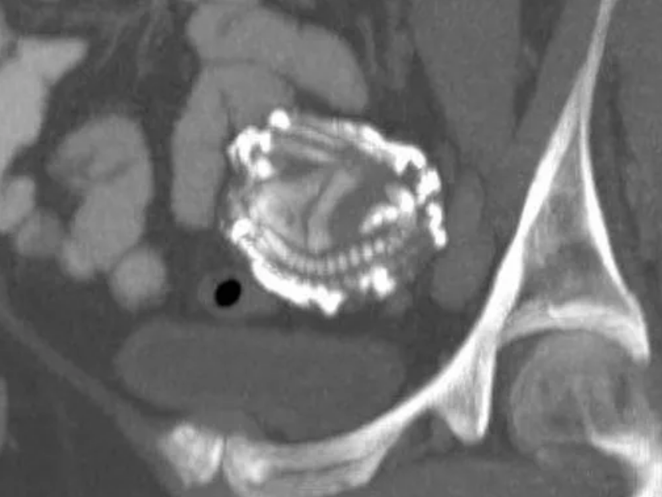

Zwei-Kilo-Tumor aus der Leber eines Babys entfernt

Ersatzknochen könnten bald aus dem 3D-Drucker kommen